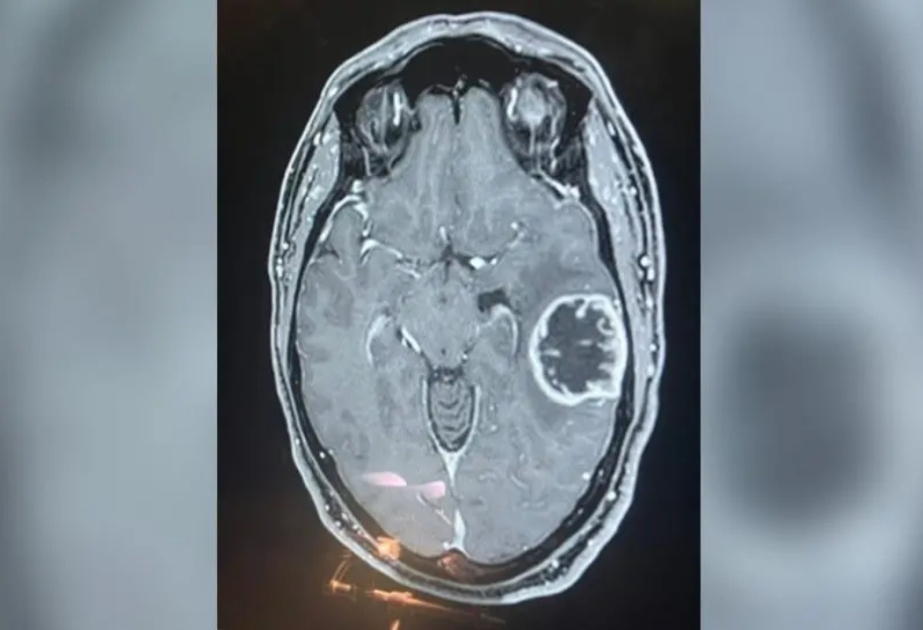

Respublika Neyrocərrahiyyə Xəstəxanasında təlim: “Tibbi tullantıların idarə edilməsi”

20.04.2026 | 16:05